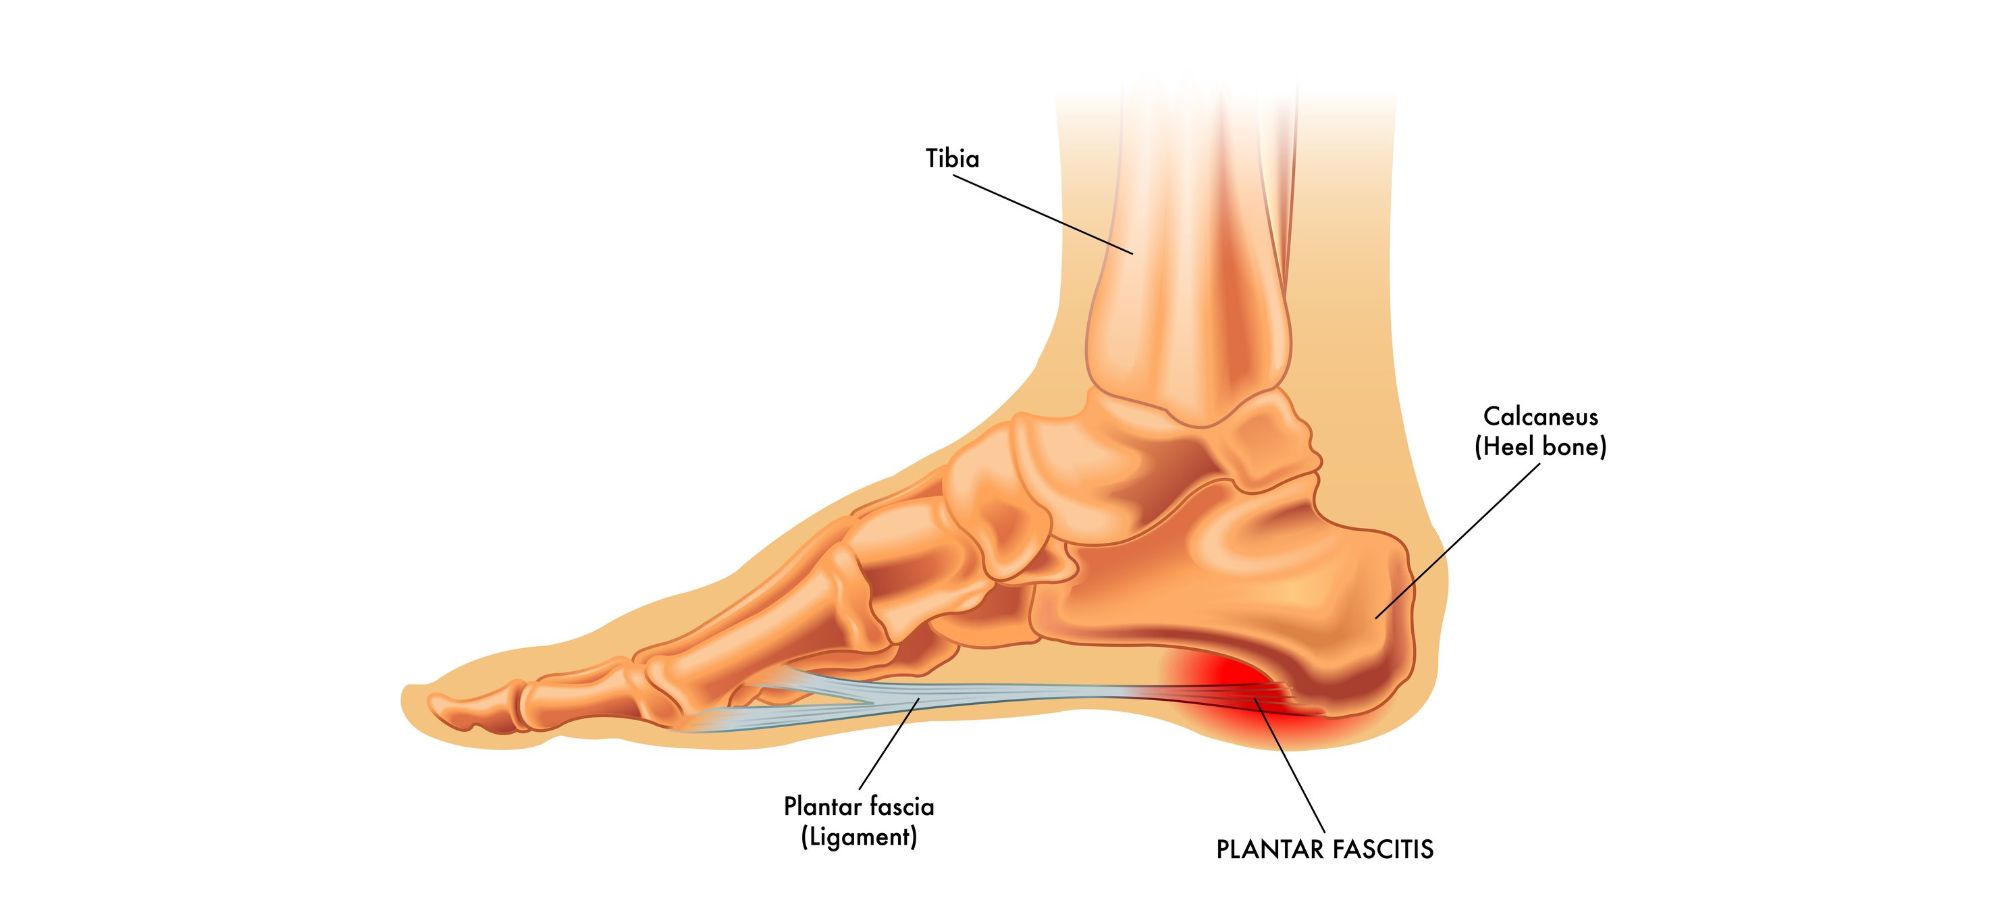

Plantar fasciitis, a common and often debilitating foot condition, affects millions of individuals worldwide. Characterized by inflammation of the plantar fascia, a thick band of tissue that runs across the bottom of your foot to your heel bone, plantar fasciitis can lead to intense heel pain and discomfort.

Before exploring the role of orthotics and insoles, it’s crucial to understand the factors contributing to pain from plantar fasciitis. The condition is often associated with overuse, improper footwear, high-impact activities, and biomechanical issues. Excessive stress on the plantar fascia can lead to microtears, inflammation, and, ultimately, pain.